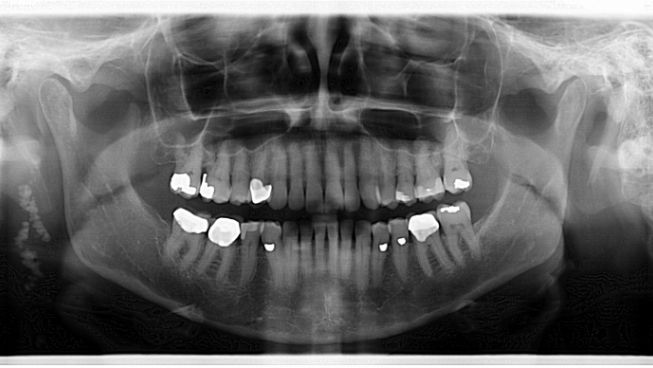

Assessment of the panoramic radiograph revealed two corrugated, irregularly shaped radiopaque masses on the right posterior angle of the mandible, each measuring approximately one inch in length. The area was not tender to palpation, and the patient had no knowledge that the lesions were there.

**See image below**1